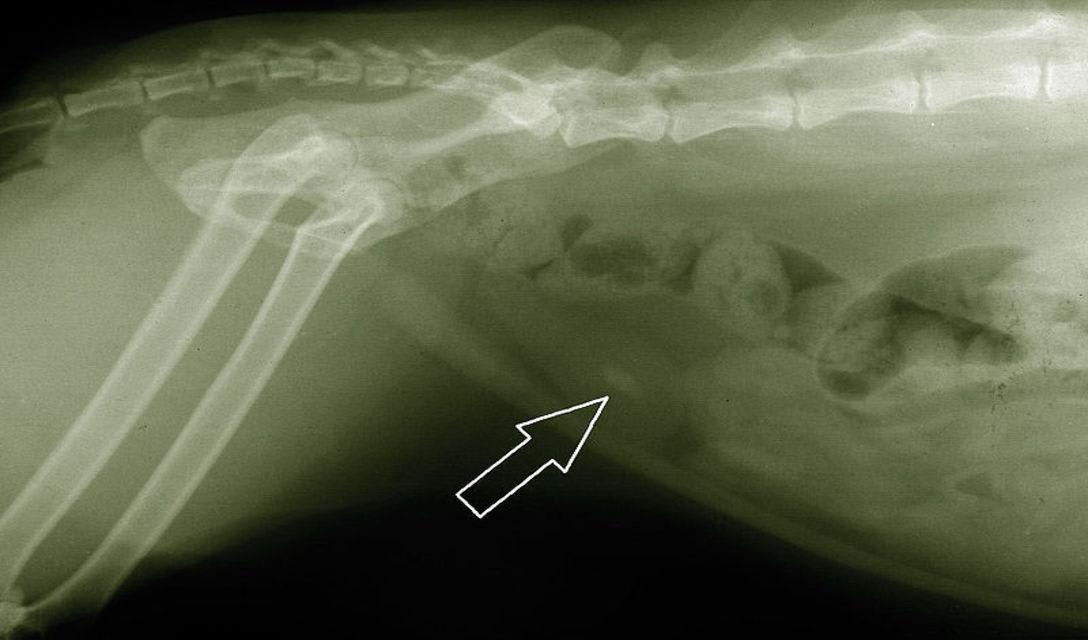

Urinary crystals are routinely diagnosed on examination of a urine sediment. Some stones can be found on routine physical exam during palpation of the urinary bladder. If the stones cannot be diagnosed through palpation, the diagnosis of bladder stones in cats is made or confirmed with abdominal x-rays or ultrasound. Most stones are radiopaque, meaning they show up on the radiographic film as obvious white circles or shapes just as bones do. A few are radiolucent and cannot be seen on the radiographic film. To confirm the presence of these types of stones, abdominal ultrasound or radiographs with a special dye may be needed. Blood work may be recommended if a cat is ill or has a urinary blockage.